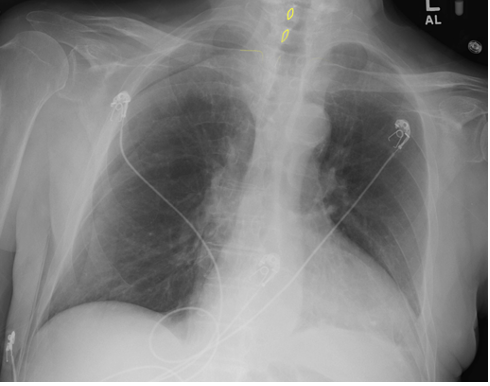

How can the scapulae determine if a CXR is PA or AP?

PA → scapulae retracted laterally so do not overlap lungs

AP → scapulae not retracted laterally so remain projected over the lung

Scapulae in AP CXR:

How well did you know this?

Scapulae in PA CXR:

How does the heart size differ in AP? Why?

Heart size exaggerated as it is an anterior structure

Magnification exaggerated further by shorter distance between x-ray source and patient

No - BUT if heart size is normal on AP, you can say it’s not enlarged